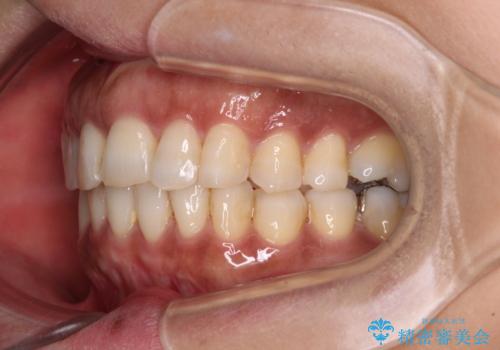

- 40代女性

- インビザライン

- 上下前歯のデコボコ改善をインビザラインにて行いたいとのことで来院された患者様です。

インビザラインをご希望のことで、IPR(歯と歯の間を削る)などによりスペースを獲得して、排列していくこととしました。

骨格的に上下顎が左右にずれていたため、正中位置は現状を維持したまま歯列不正を解消していくことになります。

なかなか装着時間が守れず、後戻りを繰り返しながら治療を進めたため、インビザライン治療期間期限ギリギリの5年弱の期間を要しました。